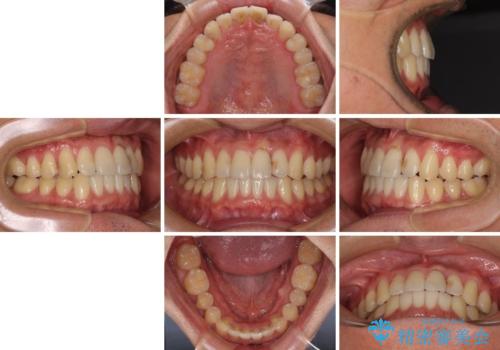

気になる前歯のデコボコをインビザラインで解消

- 前歯のデコボコを気にして来院された患者様です。

主に下顎歯列全体の後方移動とIPR(歯と歯の間を削る)によってデコボコが解消するように設計し、インビザラインにより治療を行うこととしました。

インビザライン矯正特有の、治療後半で前歯のみが強く接触する症状が発現し、咬み合わせ改善に期間を要することとなりました。